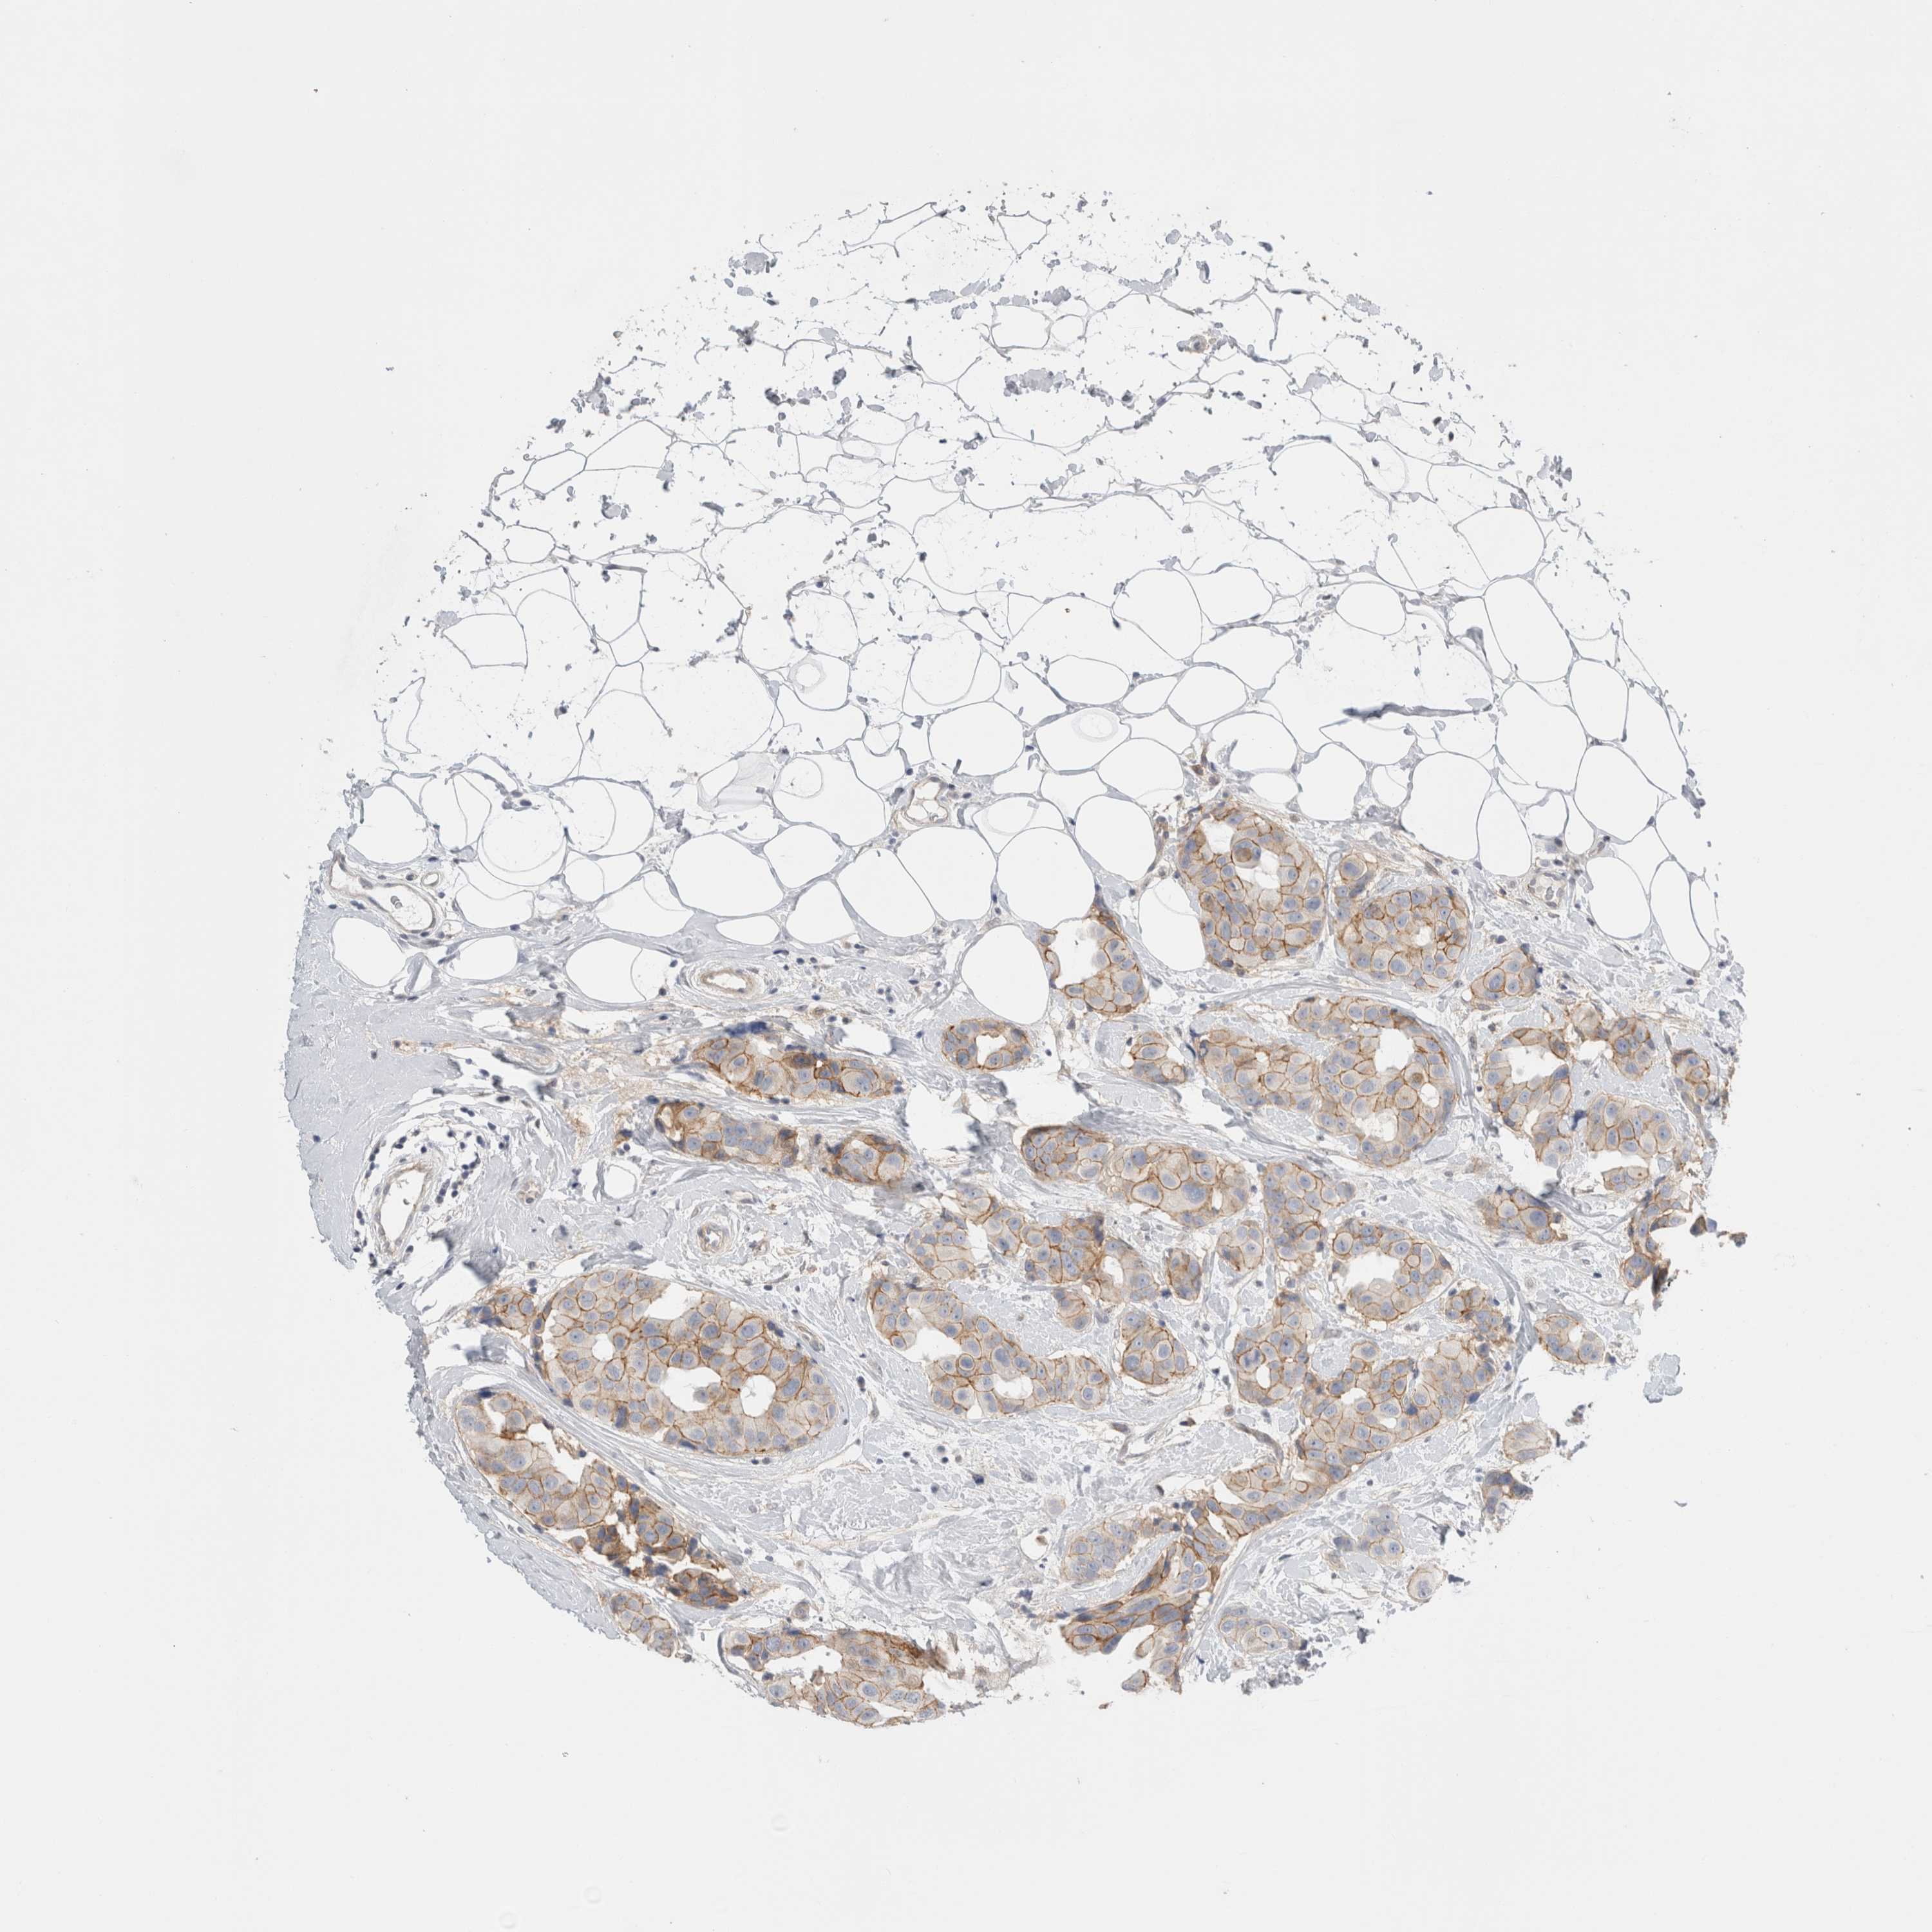

CANCER BREAST CANCER Show tissue menu

BRCA TCGA BRCA VALIDATION PROTEIN EXPRESSION